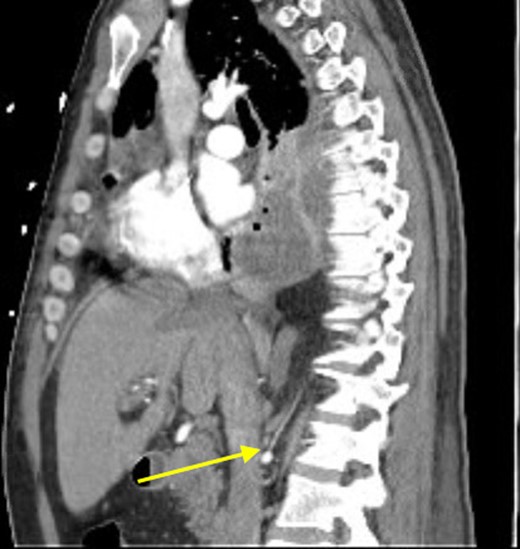

Sagittal view showing anomalous bloody supply originating from proximal right renal artery.